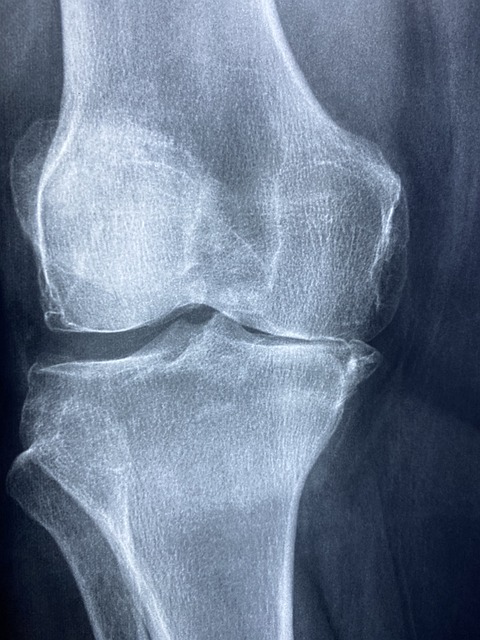

골관절염은 관절의 연골이 마모되어 발생하는 퇴행성 질환으로, 주로 무릎, 손, 엉덩이, 척추 관절에서 발생하며, 통증, 부종, 운동 범위 감소 등의 증상을 유발합니다. 콘드로이친은 이러한 골관절염의 증상을 완화하는 데 도움을 줄 수 있는 것으로 알려져 있습니다.